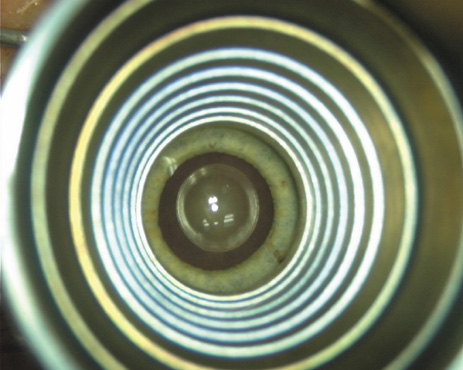

Case 1 is a 68-year-old male who presented for right cataract surgery. His refraction was −1.00 +2.25 × 80 and was recorded as reliable, consistent with his modest cataract density. Keratometry readings were 44.75 × 75 and 43.00 × 165. Corneal topography confirmed slightly more than 2.00 D of regular and slightly oblique cylinder. Consulting the nomogram, a plan was devised for a pair of LRIs to be centered over the 75-degree axis, with each incision delineating 45 degrees of arc. A single plane phaco incision was used and maintained at a size of less than 3.2 mm (Figs. 811).

Fig. 8. Steep meridian is confirmed intraoperatively by keratoscopy. In this left eye viewed from the temporal side, the “short axis” of the corneal mire is seen to be at the 75-degree meridian. (Reprinted from Hardten DR, Lindstrom RL, Davis EA. Phakic Intraocular Lenses: Principles and Practice. Thorofare, NJ: SLACK Incorporated, 2004, with permission.)